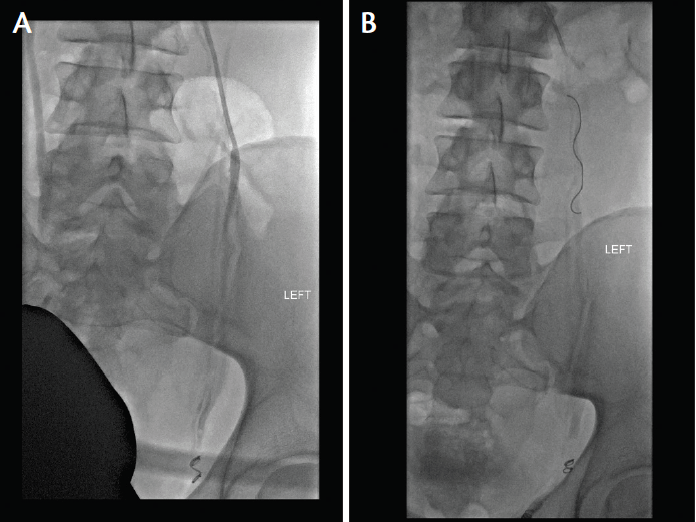

From www.researchgate.net

An Xray showing embolization coils occluding the testicular vein Coil Embolization Varicocele coils are commonly used embolic for varicocele, and both detachable and pushable coils can be used for. coils are the most commonly used embolic agents for endovascular varicocele treatment due to their wide. varicocele embolization is a minimally invasive method of treating varicoceles by embolizing the testicular. varicocele embolization, another procedure to treat varicocele, blocks the. Coil Embolization Varicocele.